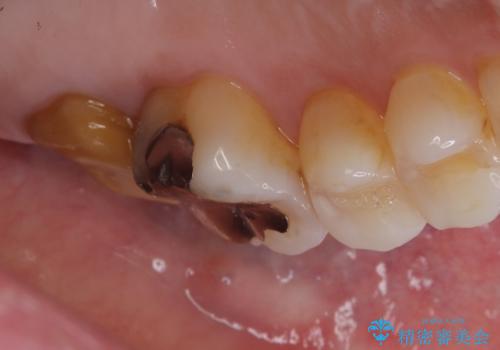

- 主訴:詰め物と歯の奥が側の境目に物がいつも溜まってしまう

レントゲン上にて、左上6番遠心にインレーと歯質の不適合を認めます。

健全歯質の残存量から、クラウンでのやり替えを提案しオールセラミッククラウン(スタンダード)でのやり替えとなりました。